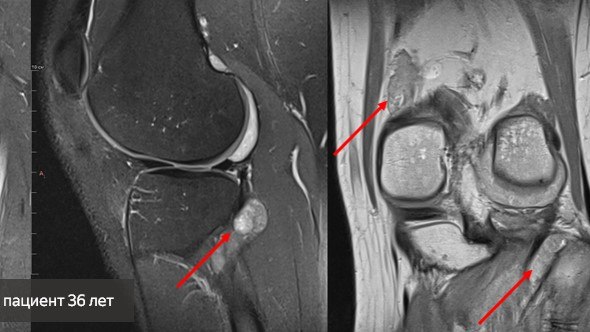

Фото со страницы vk.com/ilizarovcentre.